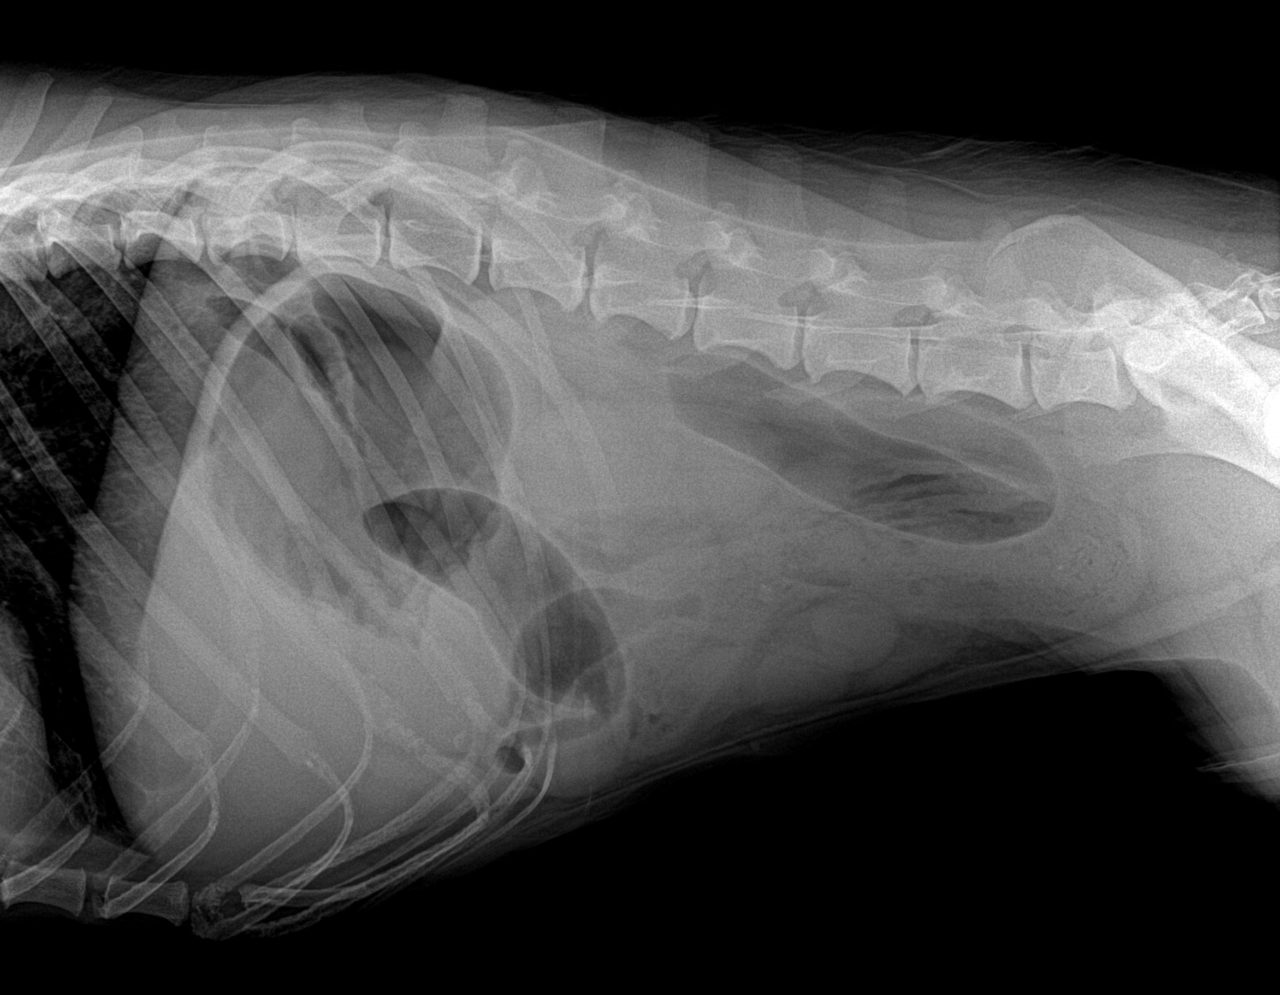

新型コロナの影響で外出の自粛からストレスが溜まっているのは人間だけでは無いようです。催吐処置、内視鏡下異物摘出、胃切開術、腸切開術とほぼ毎日、何らかの消化管内異物の患者さんが紹介されて来ます。普段は決してこんなに多くはありません。今週は1日2件、内視鏡下で異物を除去した。という日もありました。ストレスが引き金となって普段は口にしないものを誤飲をしてしまうのでしょうか?本当の原因はわかりませんが、人間社会が閉鎖された空間 ”Stay at Home”となり、このストレスが動物達にも連鎖しているのでしょうか?予防のためにも誤飲してしまう可能性のあるものは動物の近くに置かない方が良いでしょう。写真のワンちゃんは靴下を誤飲してしまい腸閉塞となり緊急手術を行った患者さんです。犬猫は我々のように言葉を持たない代わりに、人間が感じているストレスを本能的にキャッチするのでしょう。我々、人類もこのような感染力の高いウイルスとの闘いは、はじめてのことであり、なるべくストレスを抱えないで精神状態と健康状態を良い状態にキープできるよう、お互いを思いやる気持ちを持って、それぞれが自分自身をコントロール出来なければなりません。